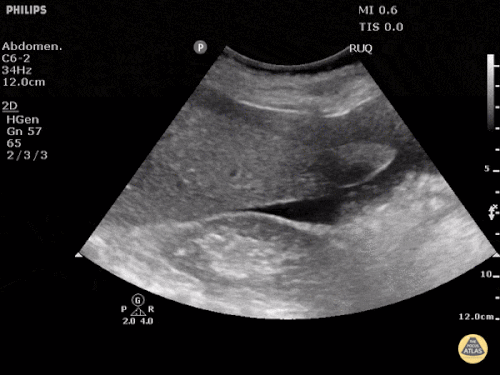

Freie Flüssigkeit

Bei der Notfallsonographie hat die Suche nach freier Flüssigkeit oberste Priorität. Diese findet man vornehmlich im sogenannten Morrison Pouch (zwischen rechter Niere und Leber), im Coller Pouch (zwischen linker Niere und Milz) sowie im kleinen Becken neben der Harnblase. Wichtig ist, dass bei der Suche nach freier Flüssigkeit im kleinen Becken möglichst senkrecht geschallt wird (Schallkopf nah an die Symphyse, erst dann kippen), da sonst die Gefahr besteht, dass man an der freien Flüssigkeit „vorbei schallt“.

Quelle: http://www.thepocusatlas.com/trauma-1 CC BY-NC 4.0